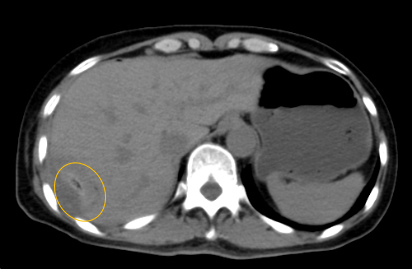

入院后,影像診療中心立即給李女士完善了CT和MR檢查,發(fā)現(xiàn)病變位于肝包膜下,臨近膈肌,消融治療過(guò)程中有并發(fā)損傷膈肌的可能,難度較大,但是采用精準(zhǔn)影像定位是可以完成的。陳寶瑩主任立即與腫瘤三病區(qū)劉金鵬主任聯(lián)系,并與影像微創(chuàng)治療小組進(jìn)行MDT討論:患者為卵巢癌肝右葉包膜下單發(fā)轉(zhuǎn)移瘤,最長(zhǎng)徑不超過(guò)3cm,患者對(duì)局部治療的主觀愿望強(qiáng)烈,符合消融治療專(zhuān)家共識(shí),遂制定了影像引導(dǎo)下局部消融治療聯(lián)合全身治療的綜合治療方案。

針對(duì)這個(gè)特殊部位的腫瘤,要想消融完全,那么膈肌損傷的風(fēng)險(xiǎn)就很高,陳寶瑩主任帶領(lǐng)影像微創(chuàng)亞專(zhuān)業(yè)組成員仔細(xì)閱讀CT圖像,設(shè)計(jì)進(jìn)針路徑,結(jié)合MR圖像確定腫瘤活性范圍,制定了周密而詳盡的消融計(jì)劃。臘月二十九,即住院第二天影像微創(chuàng)治療小組圓滿為患者完成了腫瘤微波消融治療,觀察24小時(shí)后出院回家過(guò)年。術(shù)后48小時(shí)隨訪患者無(wú)明顯不適,術(shù)后7天隨訪,患者肝功、血常規(guī)等各項(xiàng)指標(biāo)均恢復(fù)正常。